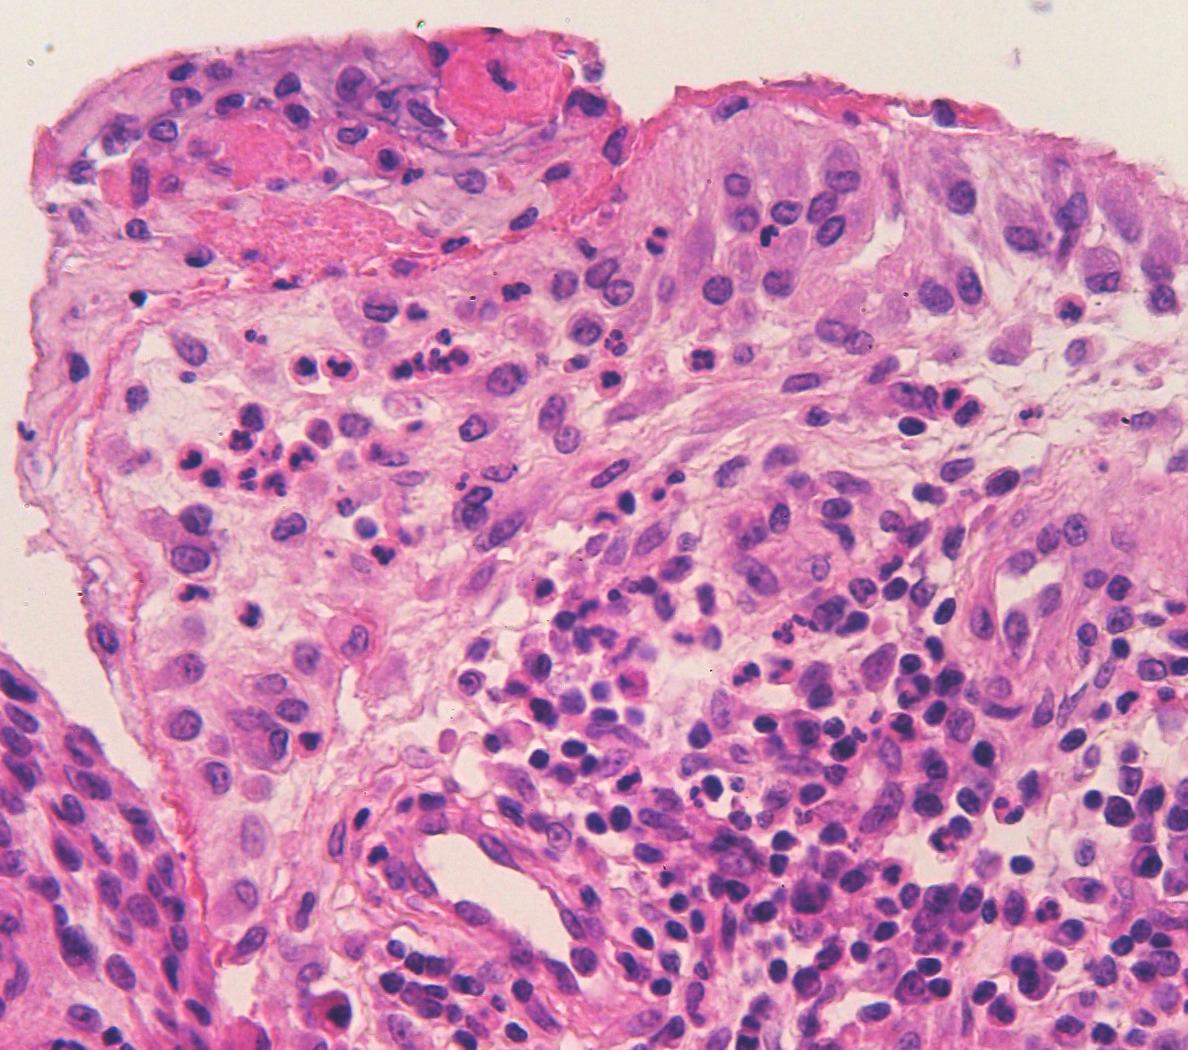

Микропрепараты: Лимфогранулематоз и Нодулярный Склероз